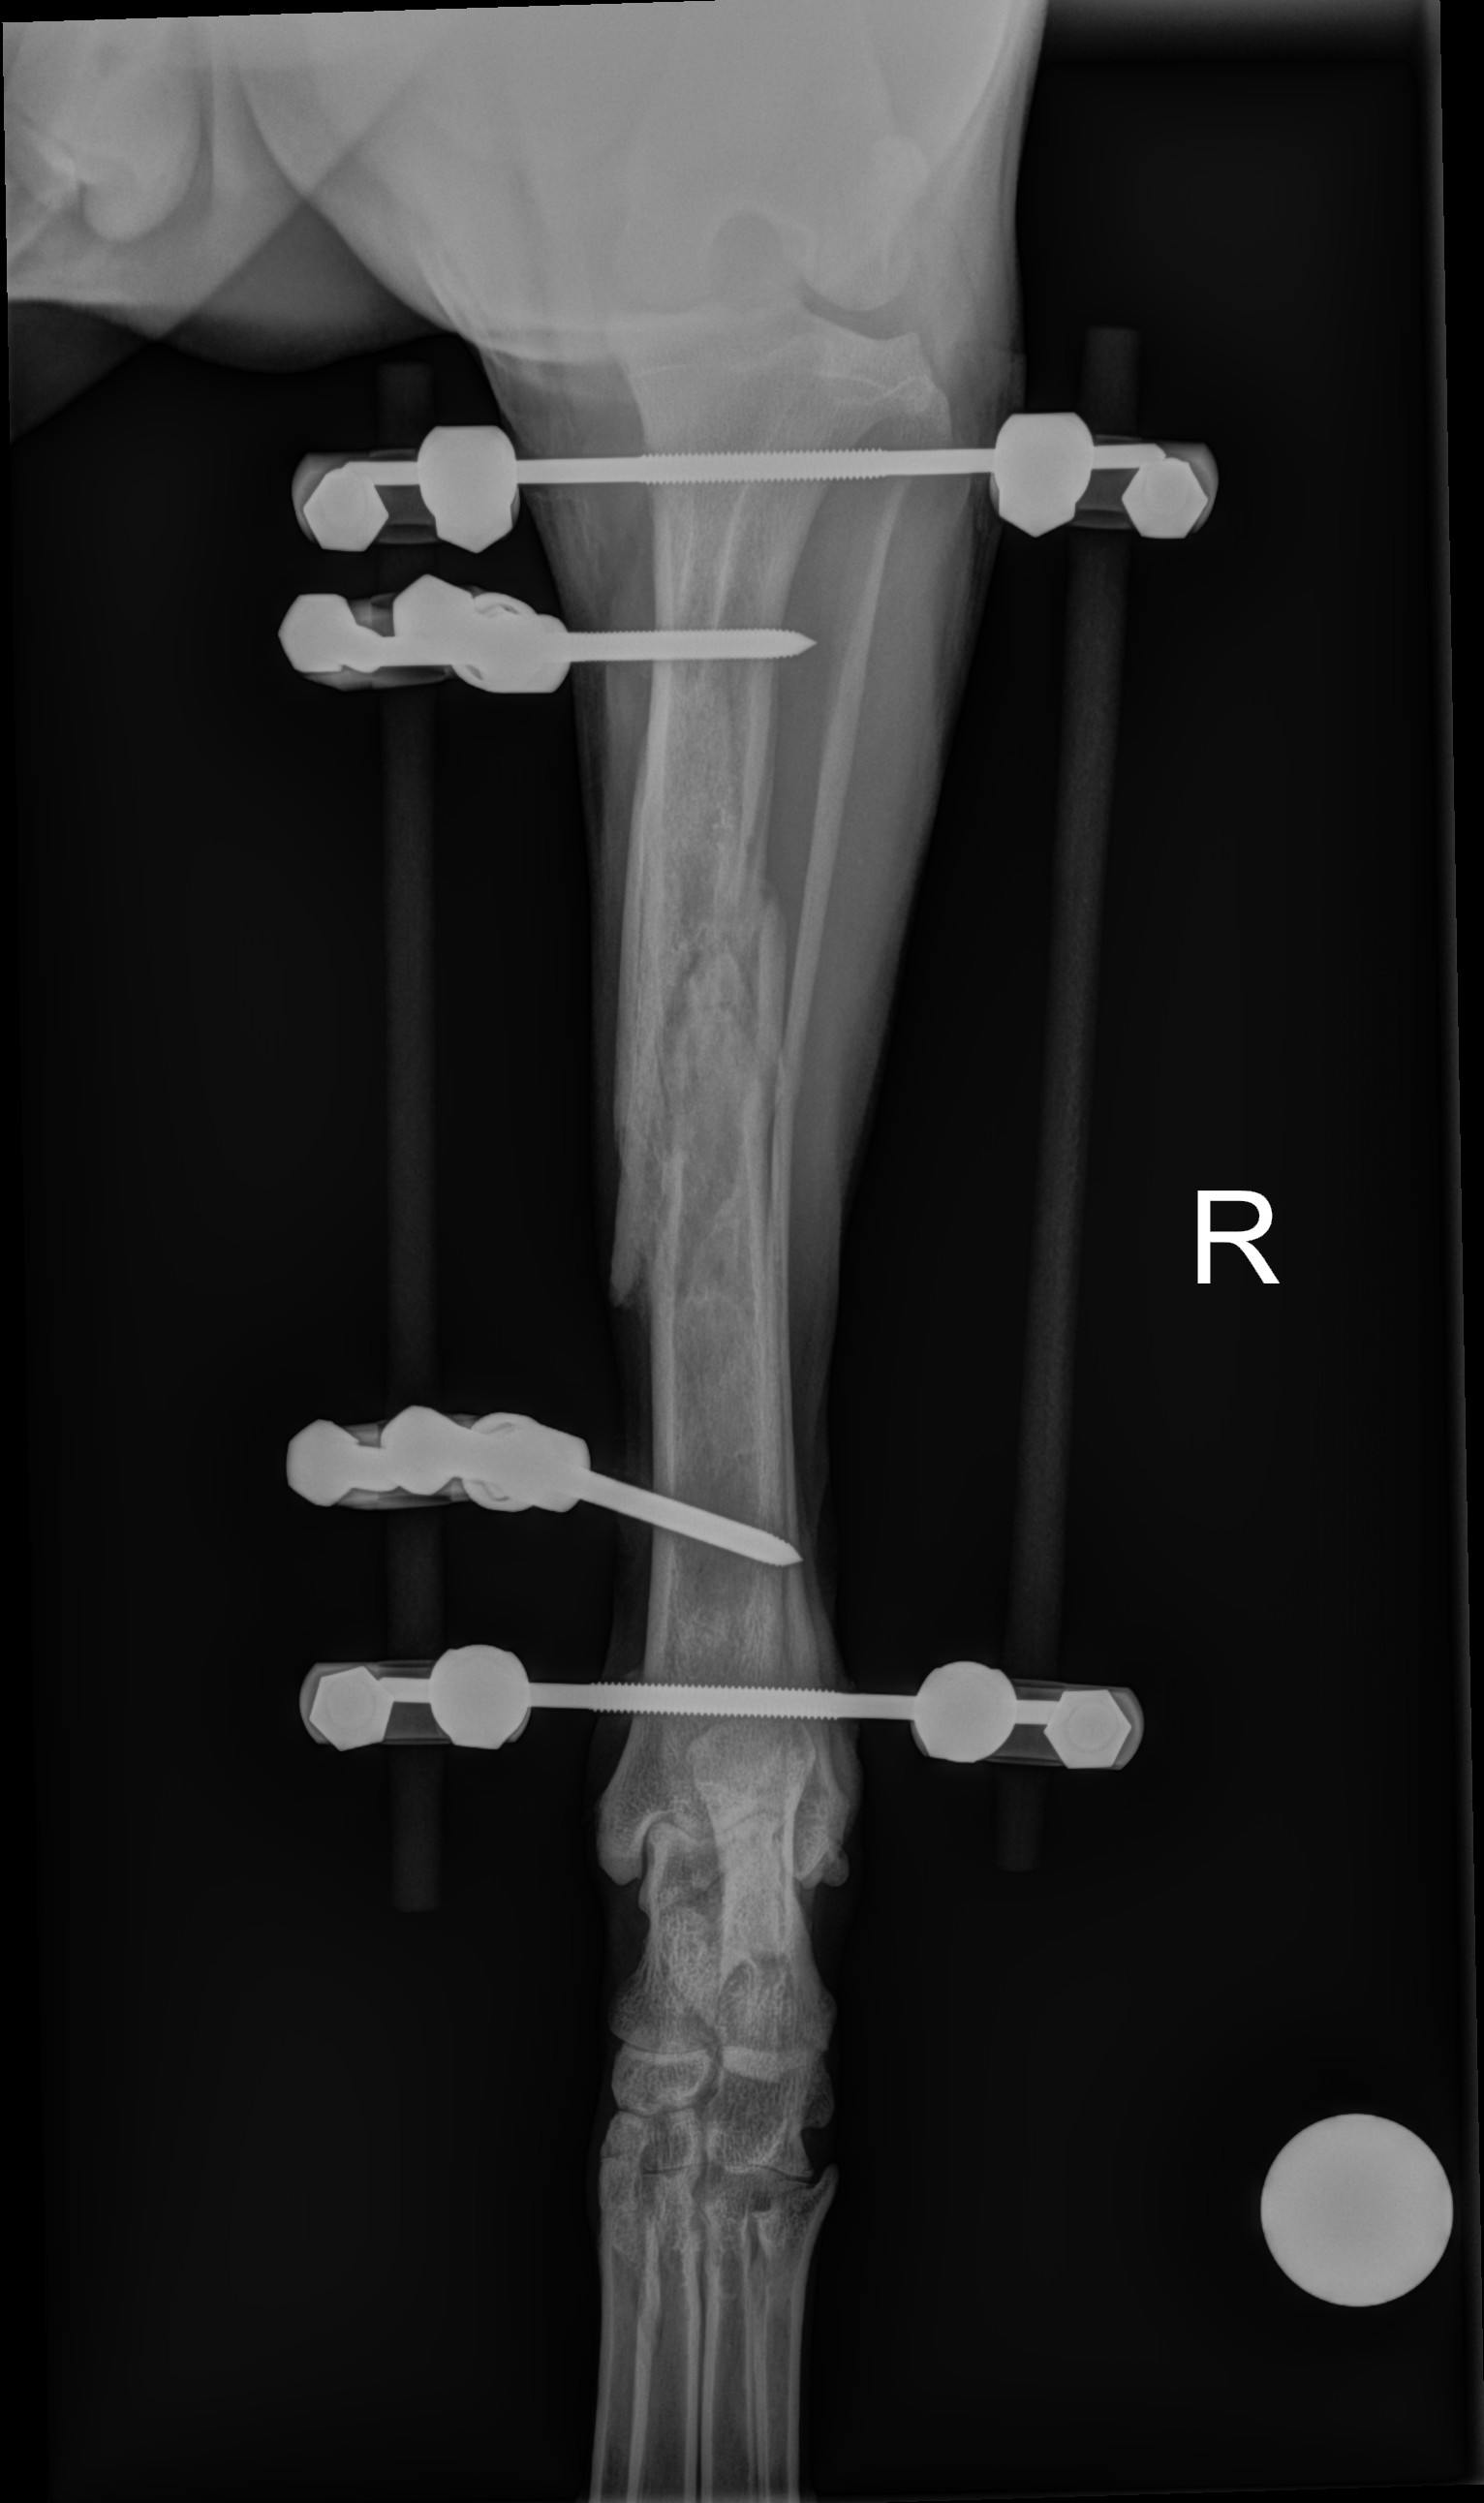

I wanted to provide an update – a month ago our family had a tragic accident where Oakley, the family dog, had her leg broken in multiple places. Oakley is a loving, active, and sweet girl. She always wants to be right by your side! She is a huge part of our family. Thank you to everyone who has helped us get her the care she needed! Oakley, has gone through surgery, had daily followed up visits, which then turned into weekly visits. It has not been an easy road but today we got some good news! The surgery has gone well! They were able to take off one side of the metal external fixator on her leg. She is still healing and recovering. She has several weeks yet to go. We are all in good spirits but wanted to provide an update! New Xray at week 4 after surgery!

Oakley is a young Walker coon hound that had her leg injured when she was out in the pasture with her family early evening on October 15th 2020. Oakley was brought to the emergency Vet to get check out, she stayed over night to get monitored as she had air & fluid in her chest cavity due to the trauma. She has several fractures in her Tibia. Oakley is needing to have surgery on her right leg. Surgery is not cheap and there will also be follow up visits that will be needing. We are asking for your help!